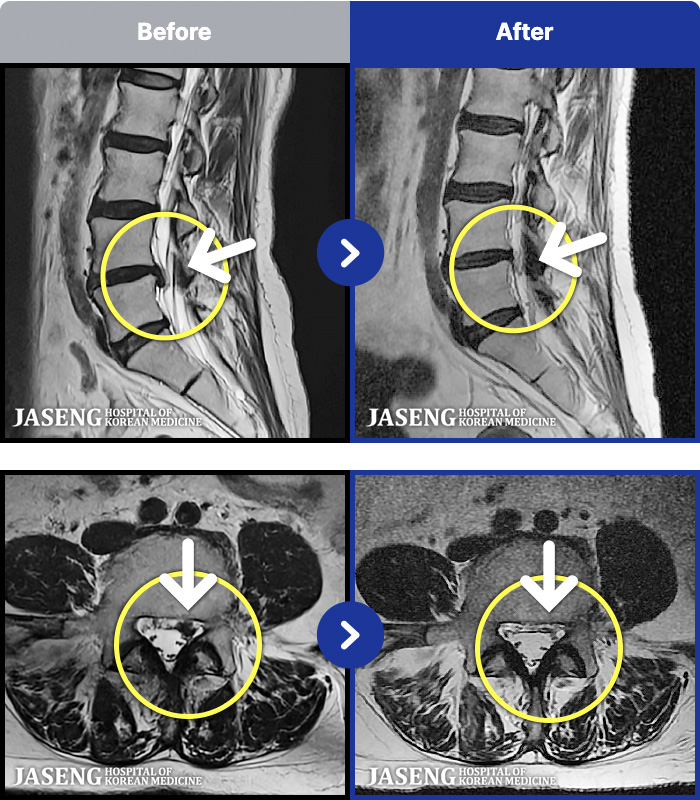

54 MRI ũ ʸ Ȯϼ.

ȯںп Ǹ ǿ ԿǾ, ο ġ ۿ Ƿ ġḦ Ͻñ ٶϴ.